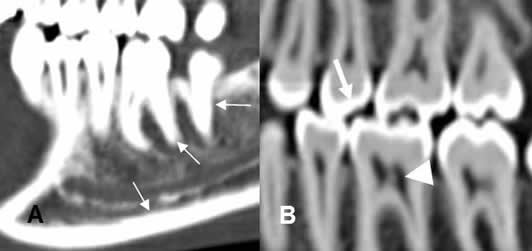

La dentina de los dientes, tiene una densidad similar a la cortical del hueso. El cemento a nivel de la corona, se identifica como una delgada capa, mas densa que la dentina. (1, 4, 6, 8). La raíz, el conducto radicular y la cámara pulpar, son menos densas y ocupan la zona central. (1, 3, 4, 8). (Fig 13).

Fig 13. Diente normal.

A y B: TAC reconstrucción sagital. Dentina, con similar densidad que la cortical del hueso. (Flechas delgadas). Cemento mas denso, en la corona del diente. (Flecha gruesa). Cámara pulpar y conducto radicular, menos densos. (Punta de flecha).